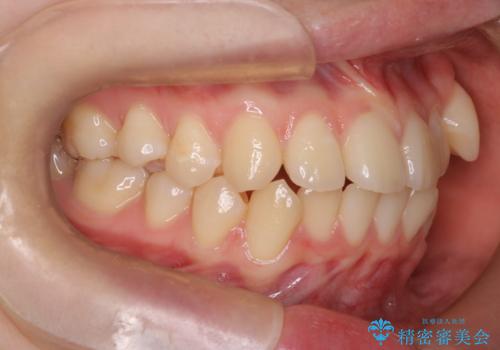

- 八重歯が気になるとのことでご相談いただきました。診察すると、歯列のスペース不足により犬歯が外側に飛び出している状態でした。このままでは歯を並べるスペースが足りないため、抜歯矯正が必要と判断。治療は目立ちにくいインビザラインで行い、歯の移動をサポートするためにゴムかけ(顎間ゴム)を併用する計画を立てました。

抜歯後、インビザラインを用いて少しずつ歯を移動させ、空いたスペースに八重歯を整列させました。さらに、ゴムかけを行うことで上下の噛み合わせを適切に調整。治療後は、八重歯が綺麗に並び、バランスの取れた歯並びと自然な噛み合わせを実現できました。患者様にも「仕上がりがとても綺麗で、口元の印象が変わった」とご満足いただきました。